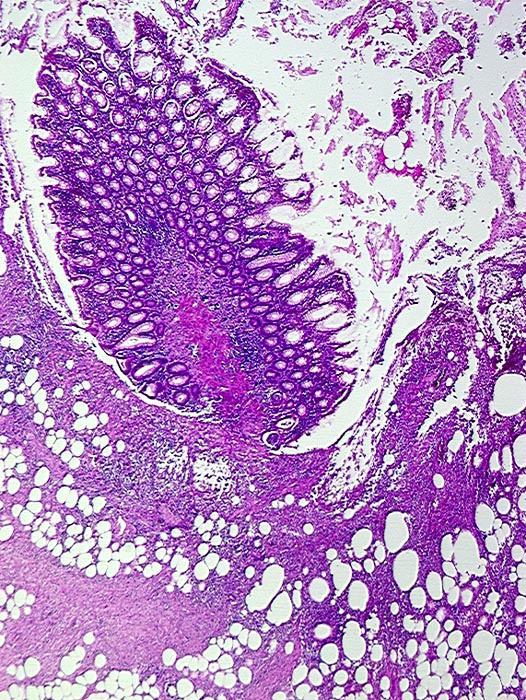

Divertikulitis

Entzündung / Reparatur

Darm, Anus

Kolon Sigma

Makroskopie

Pathologischer Befund